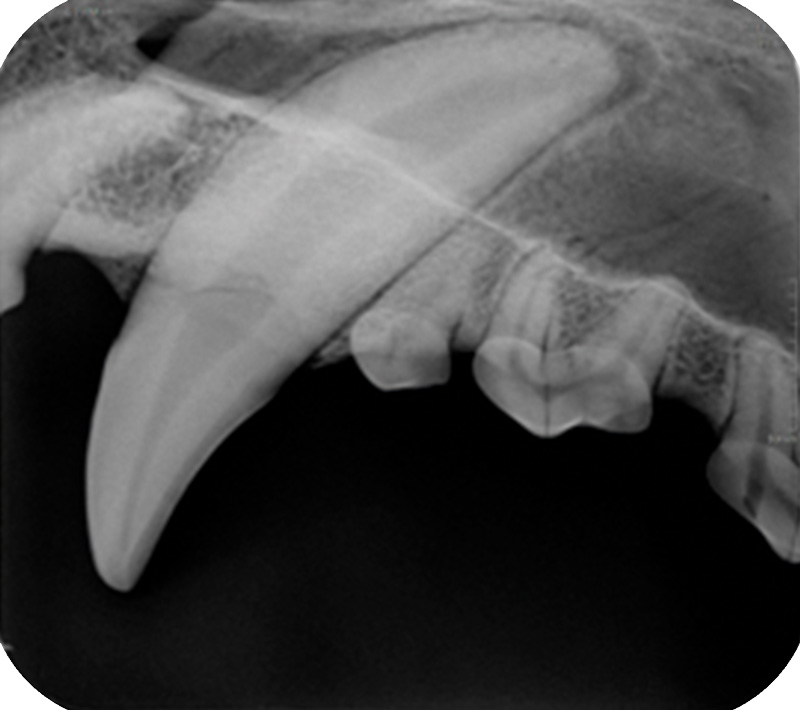

The compact, user-friendly dental CR reader for fast, high-quality digital X-Ray images - now with a higher resolution

The easy-to-use DigiVet CR PLUS Dental Reader now delivers an even more brilliant image quality. With a resolution of 21 lp / mm, the digital imaging plate system leaves nothing to be desired.